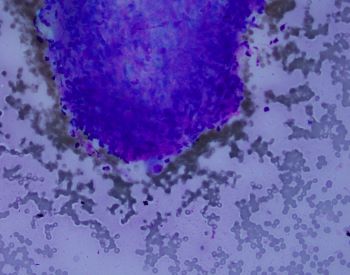

A fine needle aspiration of pancreatic head lesion/mass was performed and the specimen consists of loosely arranged small groups of spindle cells with scant cytoplasm and oval elongated and regular nuclei. Nucleoli are not seen. Ganglion cells are also present (two present in the lower half of the IHC image of the question).